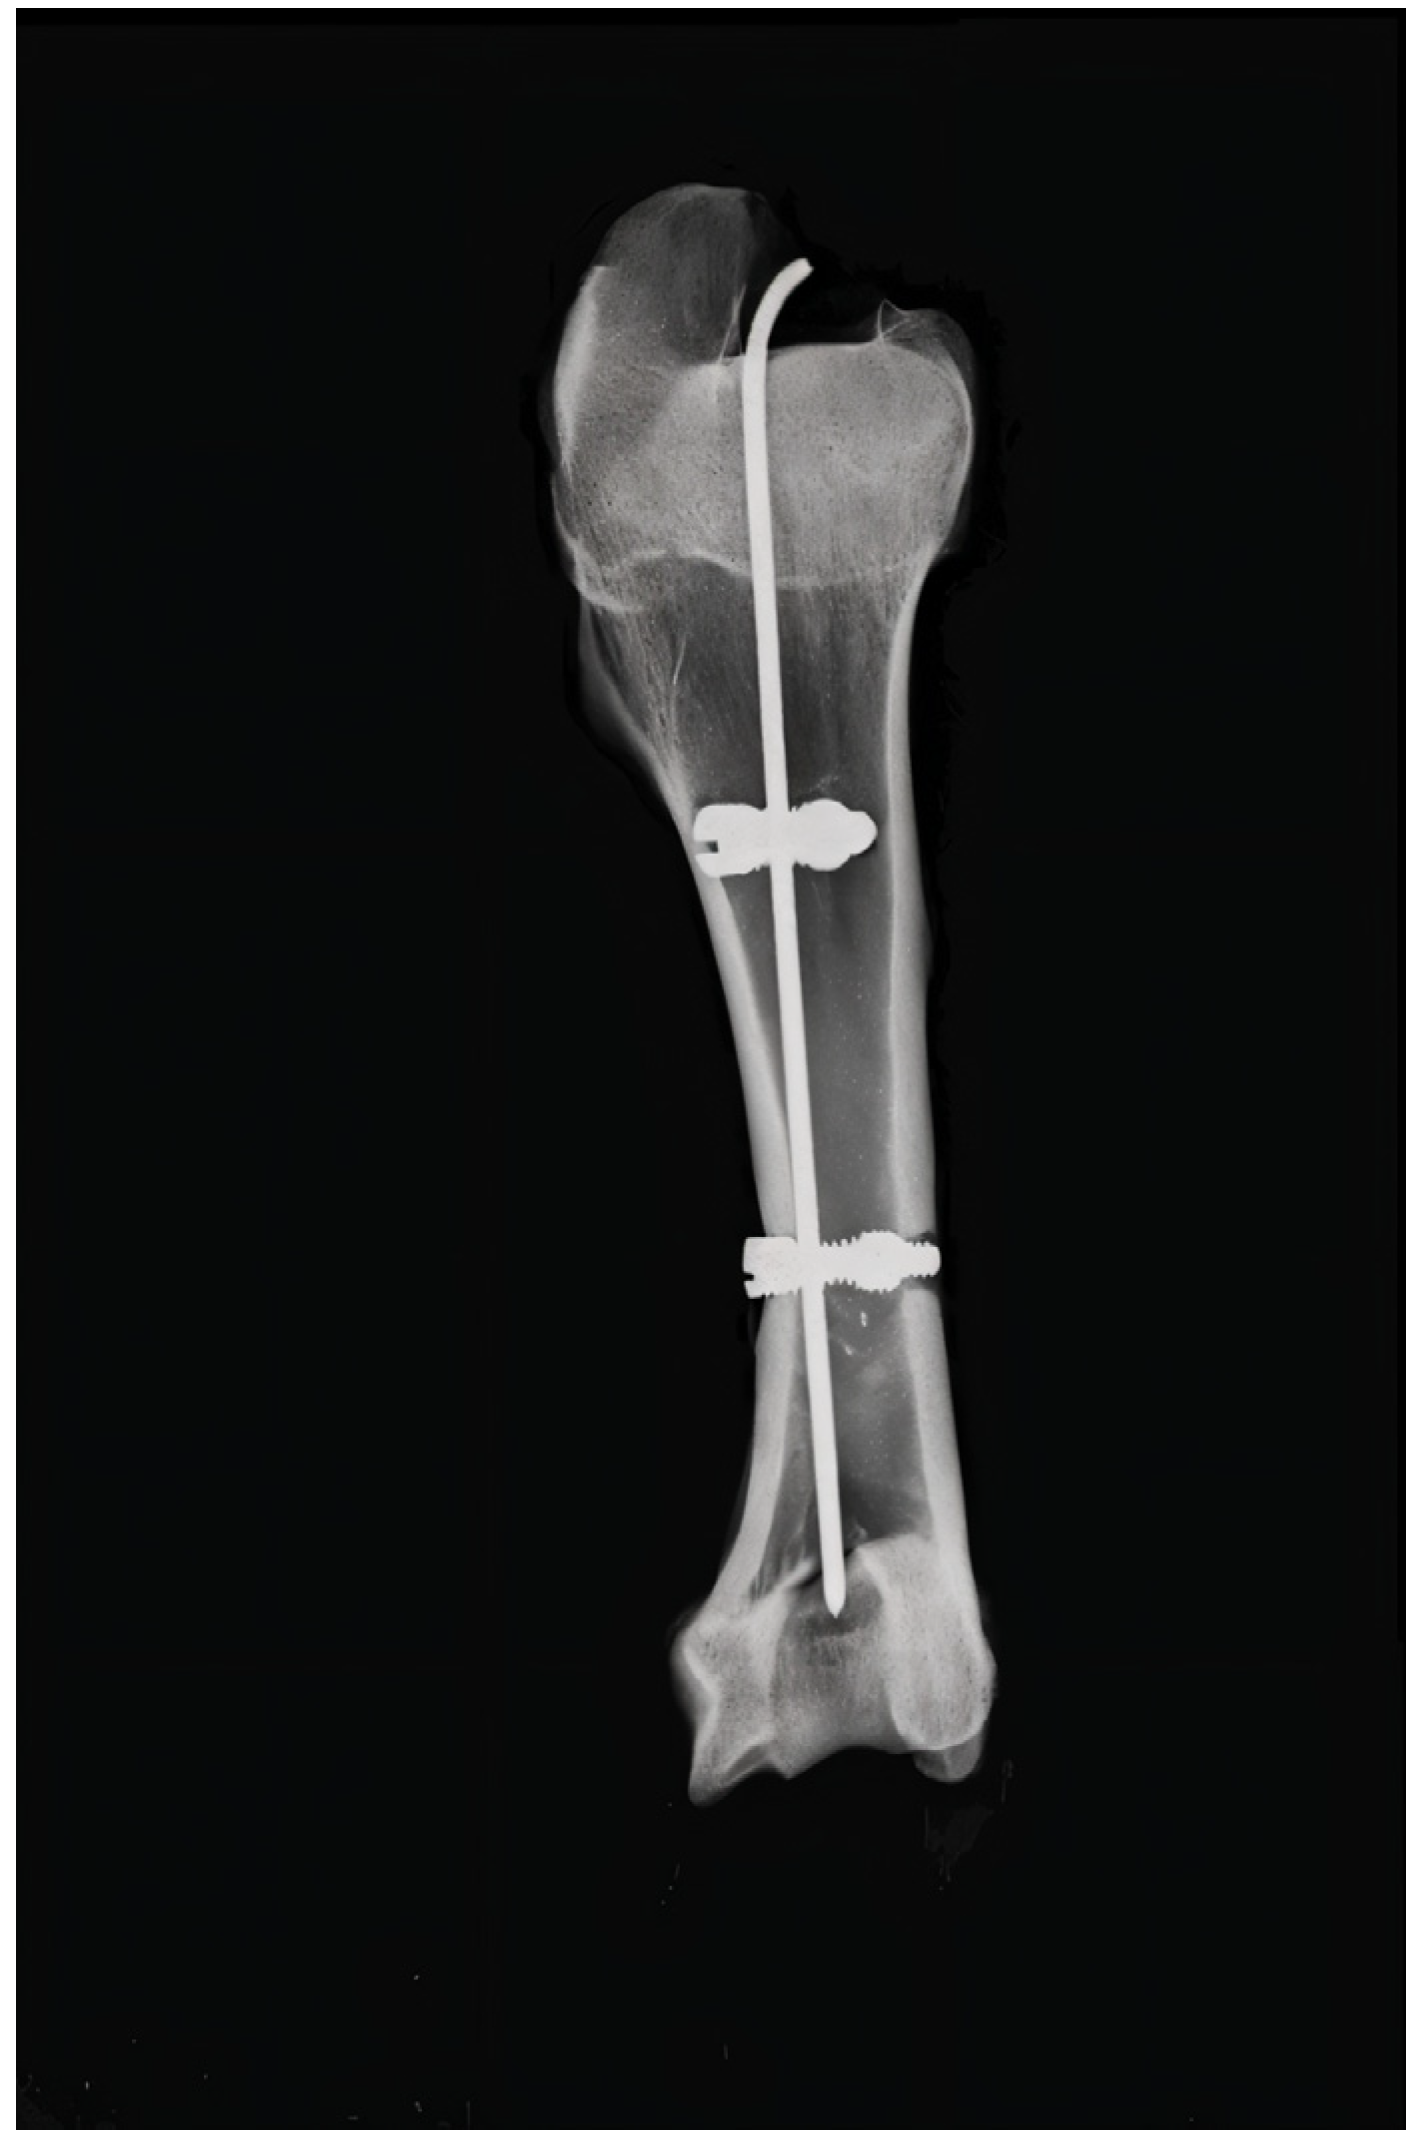

Original Locking Rod System Designed for Diaphyseal Fractures of Long Bones

2.2. Surgical Technique